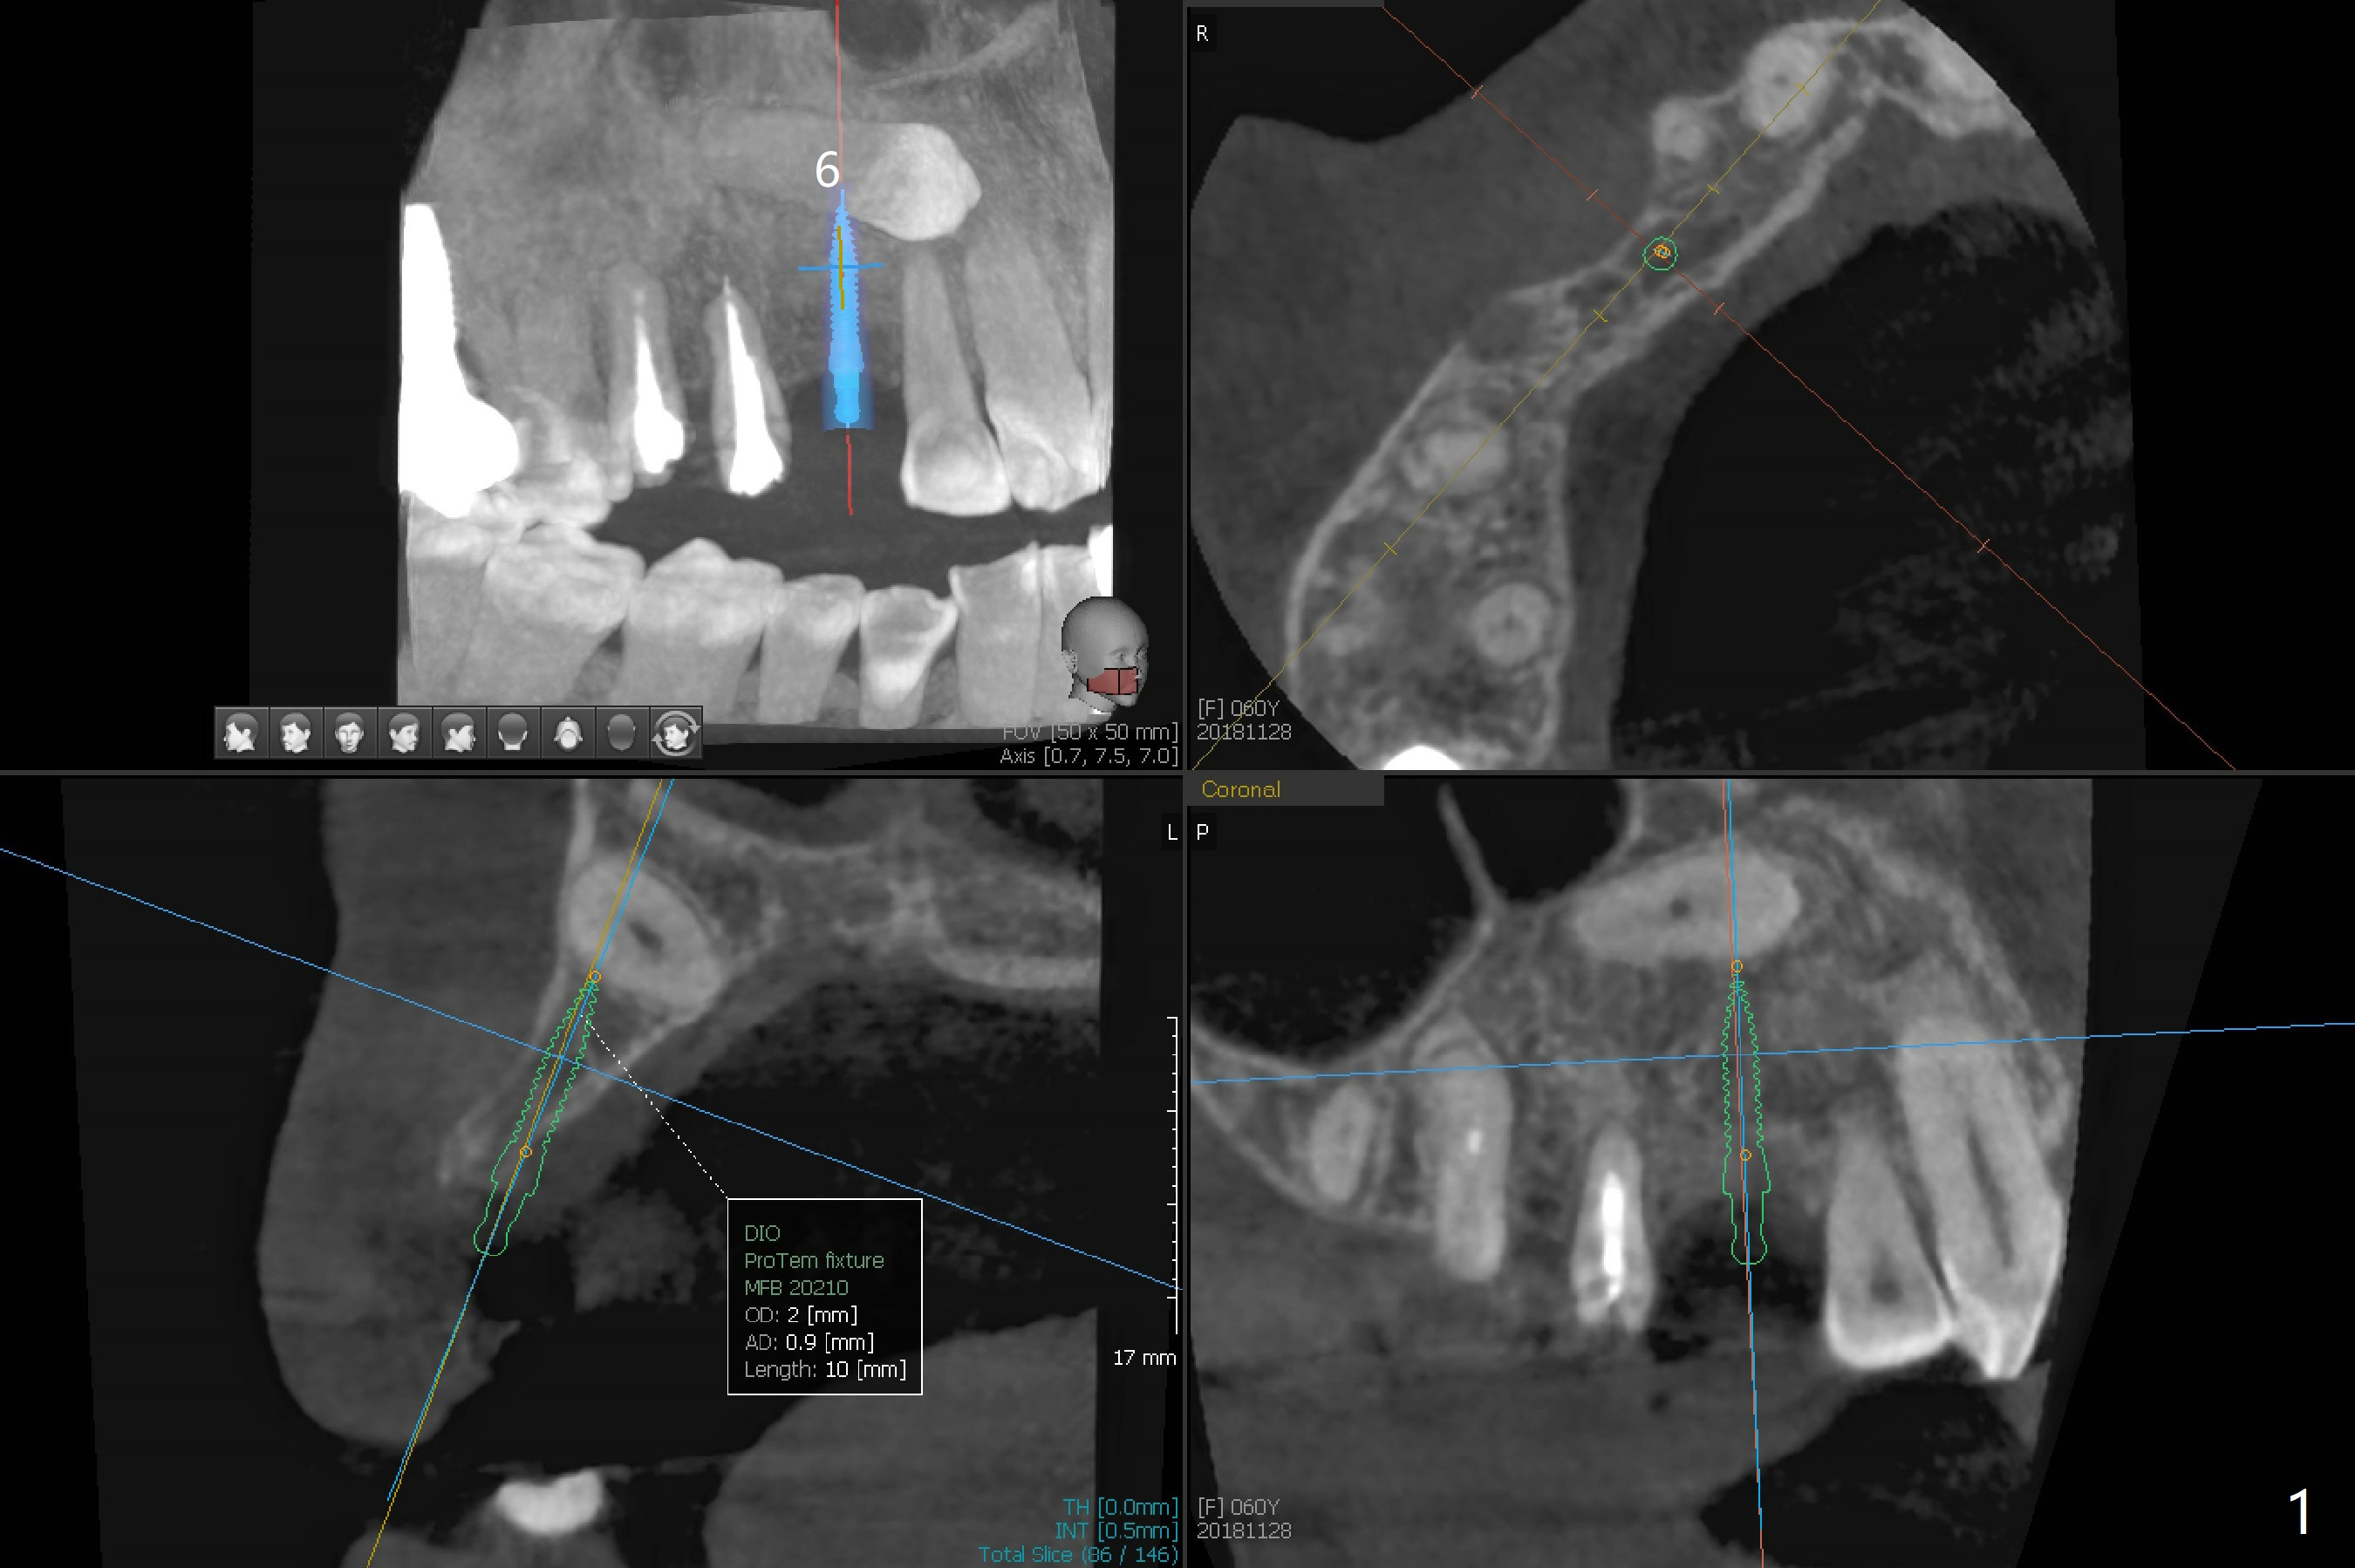

A 60-year-old woman returns for CT 4.5 months post implant removal at #6 (Fig.1). The ridge remains narrow and short because of the impacted tooth. The latter appears necessary to be extracted for a longer implant (12 or 14 mm vs. 10 mm). To accommodate a larger implant (2.5 mm vs. 2.0 mm), prepare DIO bone expander kit. But first, use an initial drill from IS Mini implant kit, followed by a parallel pin for trajectory and occlusal check. Take intraop CBCT if needed. Osteotomy will be initiated palatal (Fig.3 *, as compared to the previous osteotomy (Fig.2 <)). To reduce palatal implant thread exposure, use an implant with 4 mm cuff and place bone graft/collagen membrane. At first take impression with Alginate for wax up. In fact the stent is available. Instead PVS impression is taken for guide. The latter will be used to start initial osteotomy (2.2 mm drill for a few mm (4)), followed by 1.2 mm drill for depth.